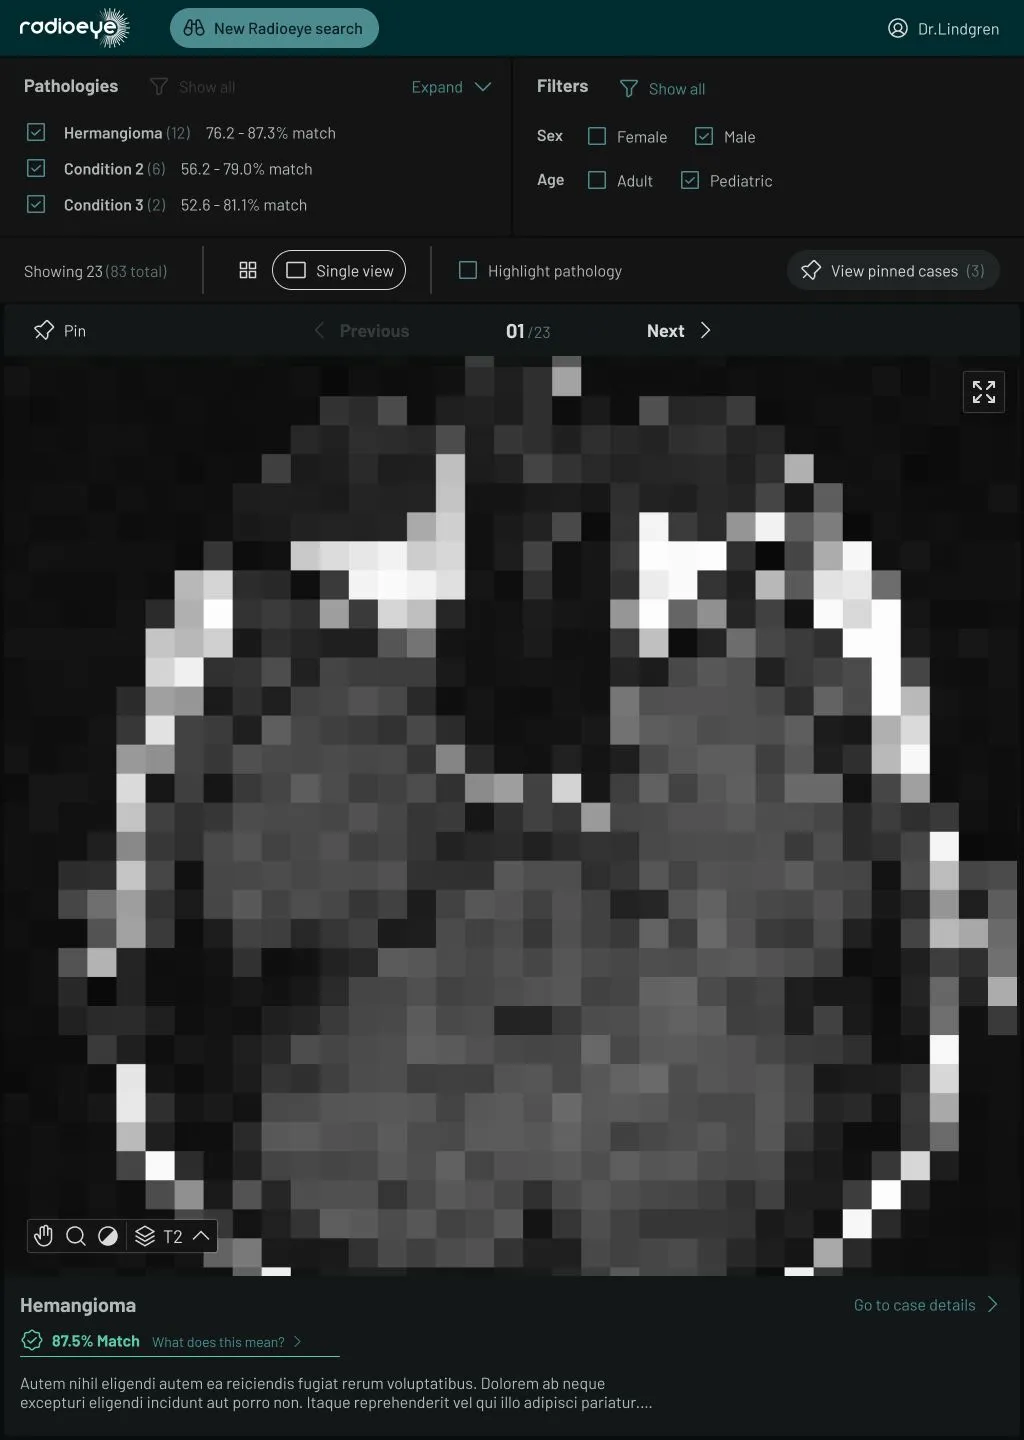

A large MRI scan of a human head, with Ui around it for navigating cases and diagnoses.

Research from Charité radiologists was used to train an ML model, aiming to aid clinicians in their diagnosis of various eye conditions. Freed from the manual research of printed text books or searching case history databases, clinicians can now upload MRI scans to the application. They then receive potential diagnoses, along with case history and fully-navigable scans – increasing vital speed and accuracy.

While bitcrowd was working with the radiologists to create the first userflows and wireframes, we introduced the concept of “case triage” to help clinicians use the cases presented to them by the ML algorithm. This meant clinicians could use a “pinned case” list for easy access to relevant cases – showing suspected matches which could include several different conditions as a differential diagnosis, improving the accuracy, speed, and completeness of the assessment.

While we were working on increasingly high-fidelity designs, we refined the layout to Radioeye’s particular needs. Here the UI needed to be both minimal and highly functional, with a “dark mode” schema to match standard MRI image viewing software.

Radioeye V1 was trialled in hospitals across Berlin. BIH then approached bitcrowd for a second iteration. V2 was conceived with the help of user feedback, offering significant improvements to the UI and overall navigation. A hierarchical list of cases was also added, grouped according to regions of the eye – allowing doctors to leverage the ML results with their own expertise.

V2’s new onboarding flow helped guide new users when using the application, and we improved the transitions between the PACS system and Radioeye. As the screen sizes commonly used by radiologists are squarer in format, we designed a landscape version of the product to enhance the user experience.